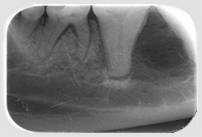

Neben der allgemeinen Untersuchung und der Untersuchung der Zahntaschen mittels Parodontalsonde sind ZAHNRÖNTGEN unumgänglich für eine komplette Diagnostik von Parodontalerkrankungen und bei Zahnresorptionen vor allem bei der Katze (FORL). Dabei werden spezielle Techniken mit Dentalfilmen wie beim Menschen verwendet.

In der Kleintier-Ordination Mittertreffling wird eine moderne digitale Entwicklung verwendet, die die Strahlenbelastung für Ihr Tier verringert. Ohne Zahnröntgen wird das Ausmaß des Knochenverlustes oft unterschätzt und bei der Katze viele Zahnresorptionen übersehen oder unterschätzt. Zudem ist bei einer wie in der Tier-Zahnheilkunde in einer Sitzung durchgeführten Wurzelbehandlung (Endodontie) eine Kontrolle durch Zahnröntgen unbedingt notwendig. Selbst Tumoren können sehr gut erkannt werden und auch die Kontrolle einer Zahnbewegung (Orthodontie) sollte durch Zahnröntgen erfolgen.

Zahnröntgen Oberkiefer Hund P4 Zahnröntgen Unterkiefer Hund normal Zahnröntgen Oberkiefer Hund dreiwurzliger P3